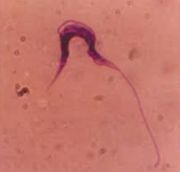

犬のL.tropicaに原因する皮膚リーシュマニア症はヒトの同症に似ており、病変は皮膚に限定して現れます。特徴は皮膚潰瘍であり、潰瘍は乾性、湿性で化膿性を帯びクレーター様であり、厚い痂皮によって覆われています。

病変の縁は紅斑性で脱毛がみられる。原虫は潰瘍辺縁の病巣にみられる大食細胞内に多数寄生しています。